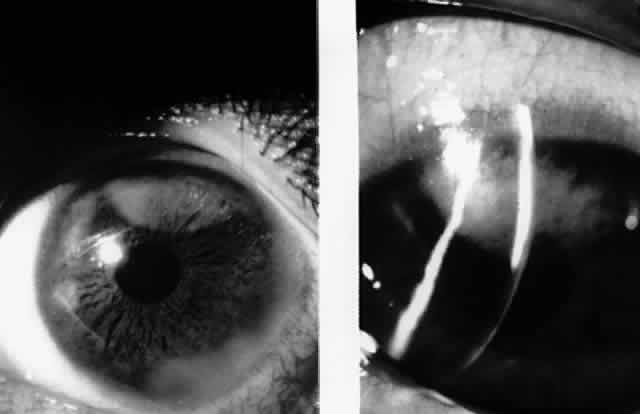

In 1986, Matoba and associates reported 7 patients with purported EBV stromal keratitis, but only 3 of the patients had clinical symptoms of IM or evidence of recent seroconversion.69 In one of the patients, heterophil antibody-positive IM preceded by 1 week the onset of chronic multifocal keratitis. When the authors first examined the patient in referral 9 months later, they found multiple, discrete, anterior stromal opacities in the patient's left eye. In another patient, bilateral, patchy, deep peripheral infiltrative keratitis and a fourfold decrease in antibody against EBV viral capsid antigen were documented at the time of referral 5 months after an “infectious mononucleosis-like illness” associated with bilateral red eyes and photophobia. In another patient, the authors state that IM preceded subepithelial infiltrative keratitis in the left eye by 1 month. When examined 8 months after onset of the keratitis, the patient's left cornea showed features of multifocal anterior stromal and deep peripheral stromal keratitis. Although the other 4 patients in this series did not show evidence of recent EBV seroconversion, their keratitis appeared similar to that of the patients with documented IM. On clinical grounds alone, Matoba and associates postulated that the development of EBV keratitis did not depend on recent EBV infection, but could occur in the chronic carrier state. To summarize the authors' findings in the combined group of 7 patients, the interstitial keratitis appeared in 4 patients as unilateral, multifocal, discrete, sharply demarcated, anterior stromal opacities, 0.1 to 2 mm in diameter, with either a blotchy pleomorphic (Fig. 2) or granular ringlike appearance (Fig. 3), in two patients as bilateral, multifocal, full-thickness or deep stromal peripheral infiltrates reminescent of luetic keratitis (Fig. 4), and in 1 patient with features of both. No patient tested had showed serologic evidence of acute systemic HSV or adenovirus infection. Both patients with keratitis restricted to the peripheral cornea had bilateral disease but lacked serologic evidence for syphilis (nonreactive MHA-TP). Five patients had mild or moderate corneal stromal vascularization. Two patients showed corneal epithelial granularity overlying the stromal opacities.

Fig. 2. Blotchy pleomorphic multifocal anterior stromal corneal infiltrates in a 25-year-old woman. (Matoba AY, Wilhelmus KR, Jones DB: Epstein-Barr viral stromal keratitis. Ophthalmology 93:746, 1986)

Fig. 3. Sharply demarcated ring opacities of the anterior corneal stroma in an 11-year-old boy. (Matoba AY, Wilhelmus KR, Jones DB: Epstein-Barr viral stromal keratitis. Ophthalmology 93:746, 1986)